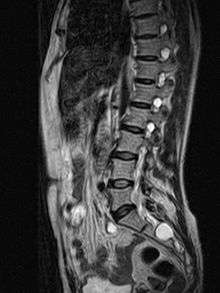

| MRI image showing a Tarlov cyst. | |

Tarlov cysts, also known as perineural cysts,[1] are type II innervated meningeal cysts, cerebrospinal-fluid-filled (CSF) sacs most frequently located in the spinal canal of the S1-to-S5 region of the spinal cord (much less often in the cervical, thoracic or lumbar spine), and can be distinguished from other meningeal cysts by their nerve-fiber-filled walls. Tarlov cysts are defined as cysts formed within the nerve-root sheath at the dorsal root ganglion.[2] Since Tarlov cysts are cysts of the spinal meninges, symptomatic Tarlov cysts by definition cause myelopathy. The etiology of these cysts is not well understood; some current theories explaining this phenomenon have not yet been tested or challenged but include increased pressure in CSF, filling of congenital cysts with one-way valves, inflammation in response to trauma and disease. They are named for neurologist Isadore Tarlov, who described them in 1938.[3]

Two most commonly used and effective examination method for Tarlov Cysts are MRI and CT. Both CT and MRI are good imaging procedures that allow the detection of extradural spinal masses such as Tarlov cysts. Magnetic resonance neurography is an emerging imaging technology based on MRI that highlights neurologic tissue. Often cysts are under reported and under diagnosed as radiologists and neurosurgeons have been traditionally taught to ignore these cysts. Patients frequently experience difficulty in diagnosis, however this is changing as Tarlov cysts have now been recognized by NORD as a rare disease.[17]

MRI

MRI, or Magnetic Resonance Imaging, is considered the imaging study of choice in identifying Tarlov cysts. MRI provides better resolution of tissue density, absence of bone interference, multiplanar capabilities, and is noninvasive. Plain films may show bony erosion of the spinal canal or of the sacral foramina On MRI pictures, the signal is the same as the CSF one.

If MRI made with a contrast medium:

- The signal in the cyst is the same as in the dural bag.

- The signal for cysts due to traumas…is a little stronger at the periphery or nerve root location

- The signal is more important for other causes: synovial cysts, dermoïdes or épidermoïdes cysts, teratomes[10][24][25]